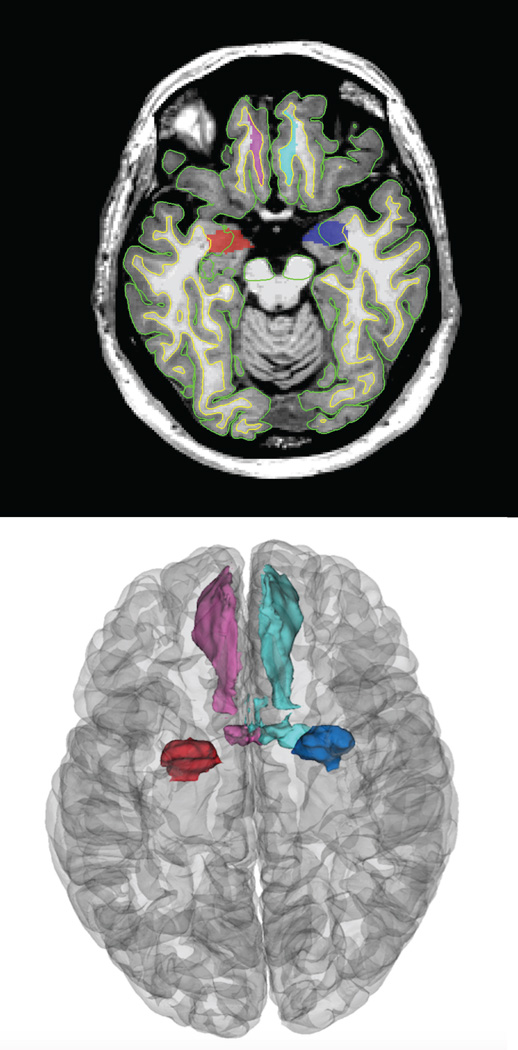

Figure 6.

Example images of the Freesurfer derived manually inspected regions of interest including the bilateral medialorbitofrontal cortices and the amygdalae.